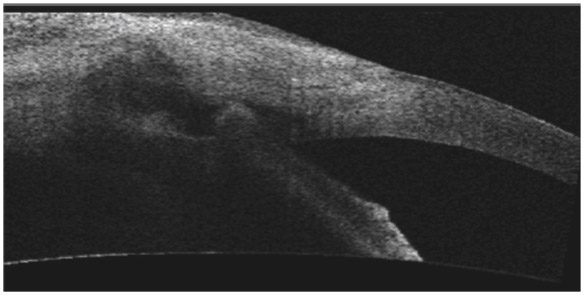

L’exploration du site de trabéculectomie peut être accessible à l’imagerie en coupe, avec des coupes méridiennes passant par la trappe de filtration ou des coupes orthogonales. Une chirurgie filtrante fonctionnelle permet d’identifier l’ouverture trabéculaire dans l’AIC, la chambre de décompression située sous le volet scléral, le volet scléral lui-même et la qualité de la bulle de filtration. Une bulle de filtration fonctionnelle prend un aspect épaissi avec une réflectivité comparable à un tissu spongieux témoignant de l’imprégnation de l’humeur aqueuse (HA) dans la conjonctive (fig. 10-16) [5, 7, 10].

La conjonctive peut prendre un aspect peu épaissi mais fonctionnel, et parfois donner une bulle de filtration volumineuse avec visualisation d’une collection plus ou moins importante d’HA sous la conjonctive et un aspect fibrosé de la conjonctive qui ne laisse plus échapper l’HA en arrière (fig. 10-17).

Fig. 10-16 Aspect en OCT d’une trabéculectomie avec bulle de filtration conjonctivale d’aspect fonctionnel.

Fig. 10-17 Bulle de filtration d’aspect fibrosé au niveau conjonctival (OCT).